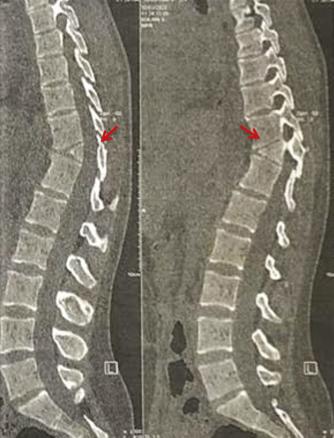

Une patiente de 25 ans, sans antécédents pathologiques particuliers, consulte pour des dorsolombalgies mécaniques avec une irradiation intercostale, sans déficit moteur ou sensitif. L’examen clinique met en évidence une hypercyphose dorsale et une hyperlordose lombaire. Les scanners dorsolombaires (fig. 1 et 2) objectivent une division complète du corps vertébral D11 en hémivertèbre dite « en aile de papillon ». La patiente est mise sous traitement symptomatique associé au renforcement des muscles paravertébraux et respiratoires avec une bonne évolution.

Il est important de comprendre les caractéristiques radiographiques des vertèbres papillon pour les distinguer des autres processus pathologiques (fracture, métastase, syringomyélie et maladie de Charcot). Un examen attentif des vertèbres adjacentes montre des caractéristiques de déformation de longue date, telles qu’un allongement exagéré des marges antérieures et un disque intervertébral normal. De plus, les vertèbres papillon causent généralement moins de cyphose. Plusieurs publications ont établi un lien entre les vertèbres papillon et les lombalgies1,9,10 dont le traitement est généralement conservateur. La cause de la lombalgie chez un patient avec des vertèbres papillon peut être sans rapport avec l’anomalie structurale et nécessite donc des recherches supplémentaires. Cependant, le traitement de la lombalgie dans la plupart des cas est généralement conservateur.